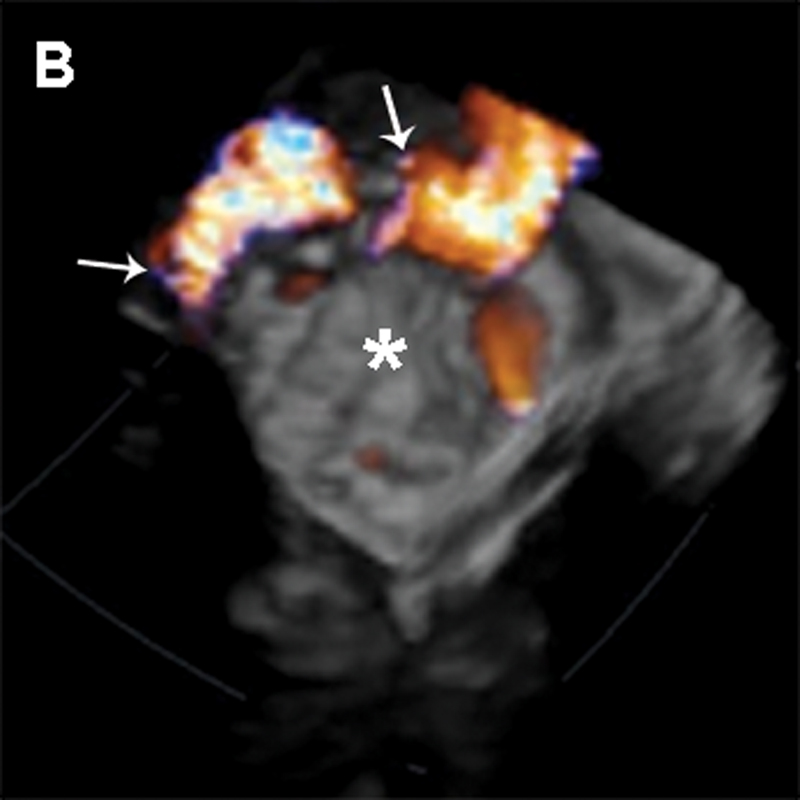

فحوصات تشخيصية لبعض امراض القلب والشرايين التاجية